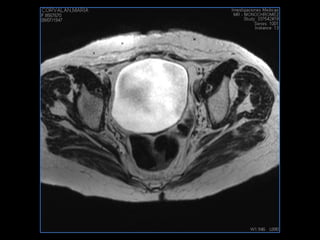

PROTOCOLO pelvis SAG T2, Y FAT SAT (FINOS) AXIAL T1  AX FAT SAT CON   GADOLINIO :  AX T1 Y COR T1 SAT: NO  FASE: RL THK: 3MM  COIL:  GAP: (FACTOR 1.4) 1MM FOV: 40 CM NEX:2 SINCRONIZACION RESPIRATORIA EN 3 O 4 CICLOS ALE